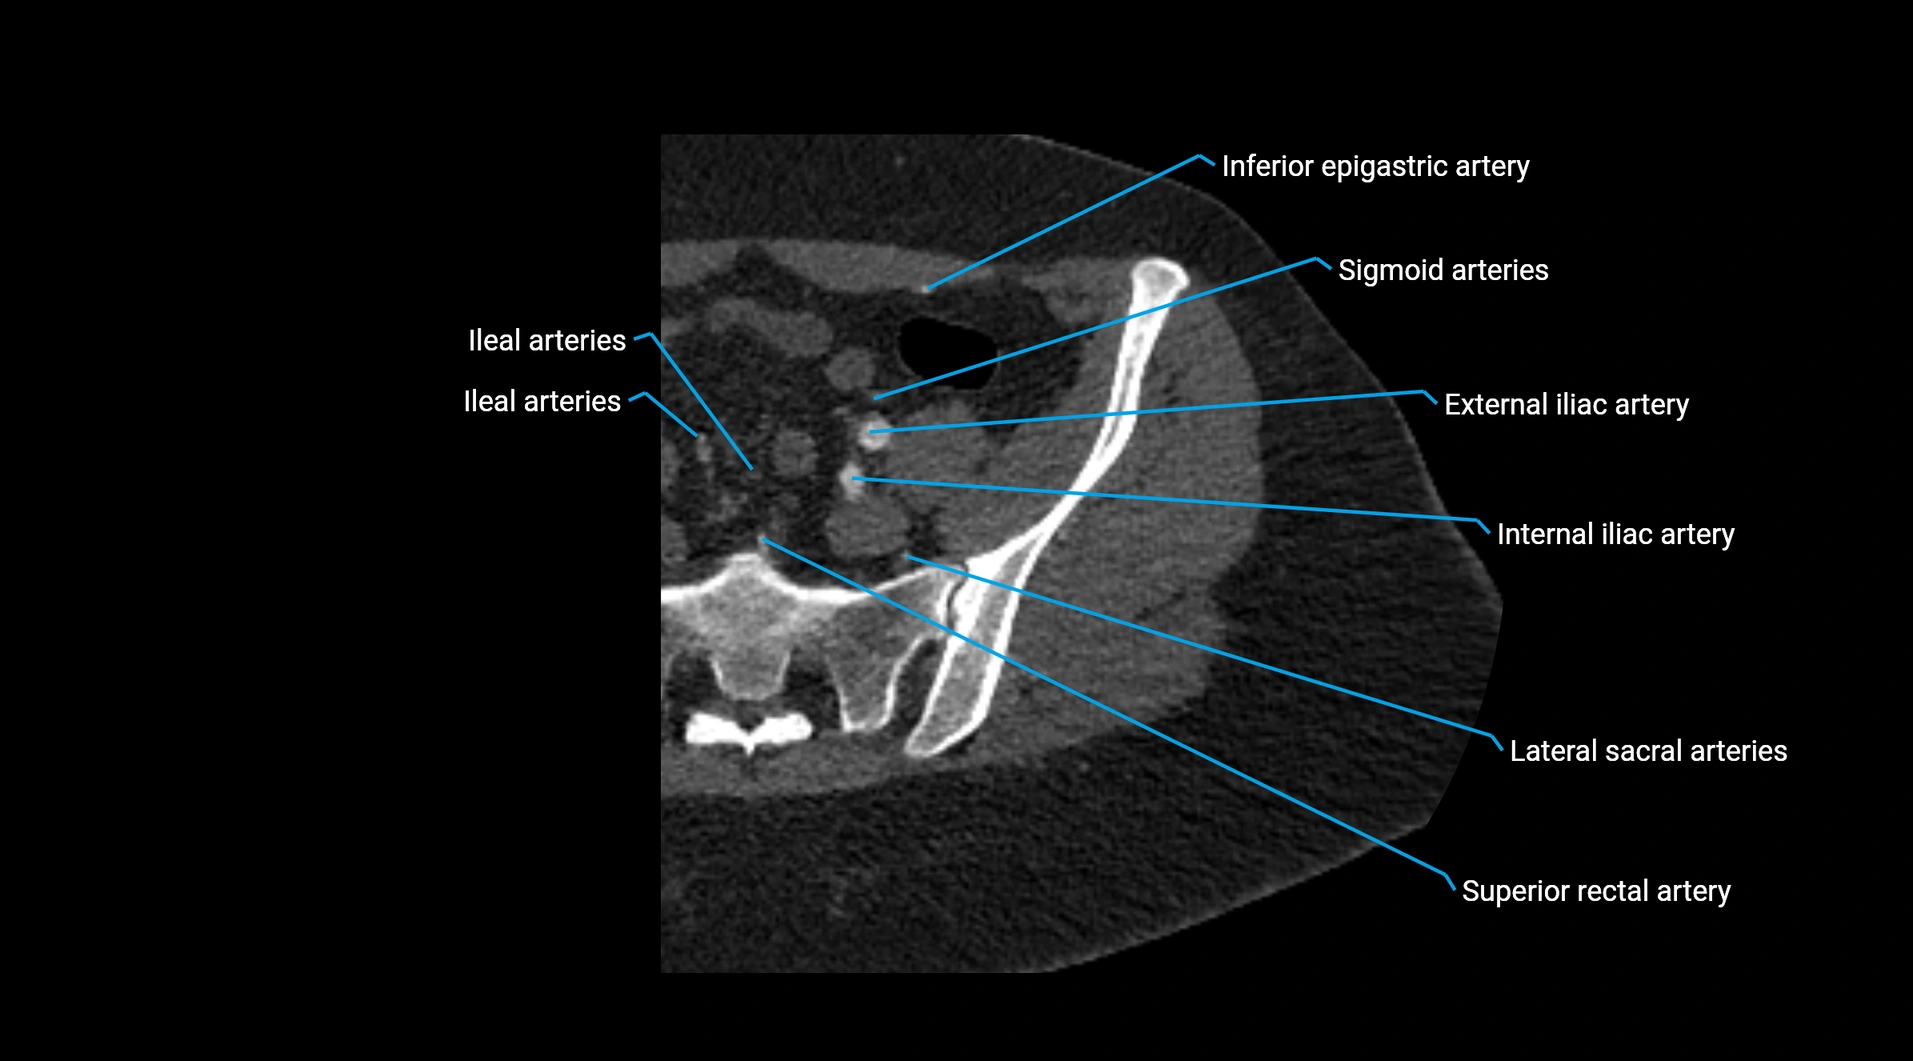

Contrast-enhanced CT (CTA):

• Gold standard for abdominal aortic imaging

• Provides excellent detail of lumen, wall, aneurysm, thrombus, and branch vessels

• Multiplanar and 3D reconstructions help in aneurysm measurement, stent graft planning, and dissection evaluation

• Unpaired visceral branches: celiac trunk, superior mesenteric artery (SMA), inferior mesenteric artery (IMA)

• Paired visceral branches: middle suprarenal arteries, renal arteries, gonadal arteries (testicular or ovarian)

• Parietal branches: inferior phrenic arteries, lumbar arteries, median sacral artery

• Terminal branches: right and left common iliac arteries